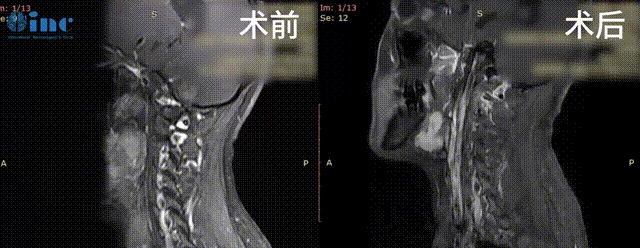

30岁女性-延髓-颈髓海绵状血管瘤

34岁男性-脑干延髓-颈髓室管膜瘤WHO2级

术后一个多月,患者行走自如已基本恢复正常生活。